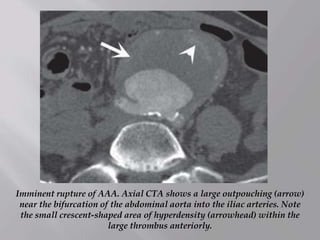

Imminent rupture of AAA. Axial CTA shows a large outpouching (arrow)

near the bifurcation of the abdominal aorta into the iliac arteries. Note

the small crescent-shaped area of hyperdensity (arrowhead) within the

large thrombus anteriorly.